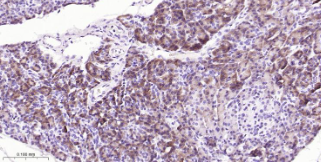

Immunohistochemical analysis of paraffin embedded human liver tissue slide using IHC0497H (Human CBS IHC Kit).

Immunohistochemical analysis of paraffin embedded human pancreas tissue slide using IHC0497H (Human CBS IHC Kit).